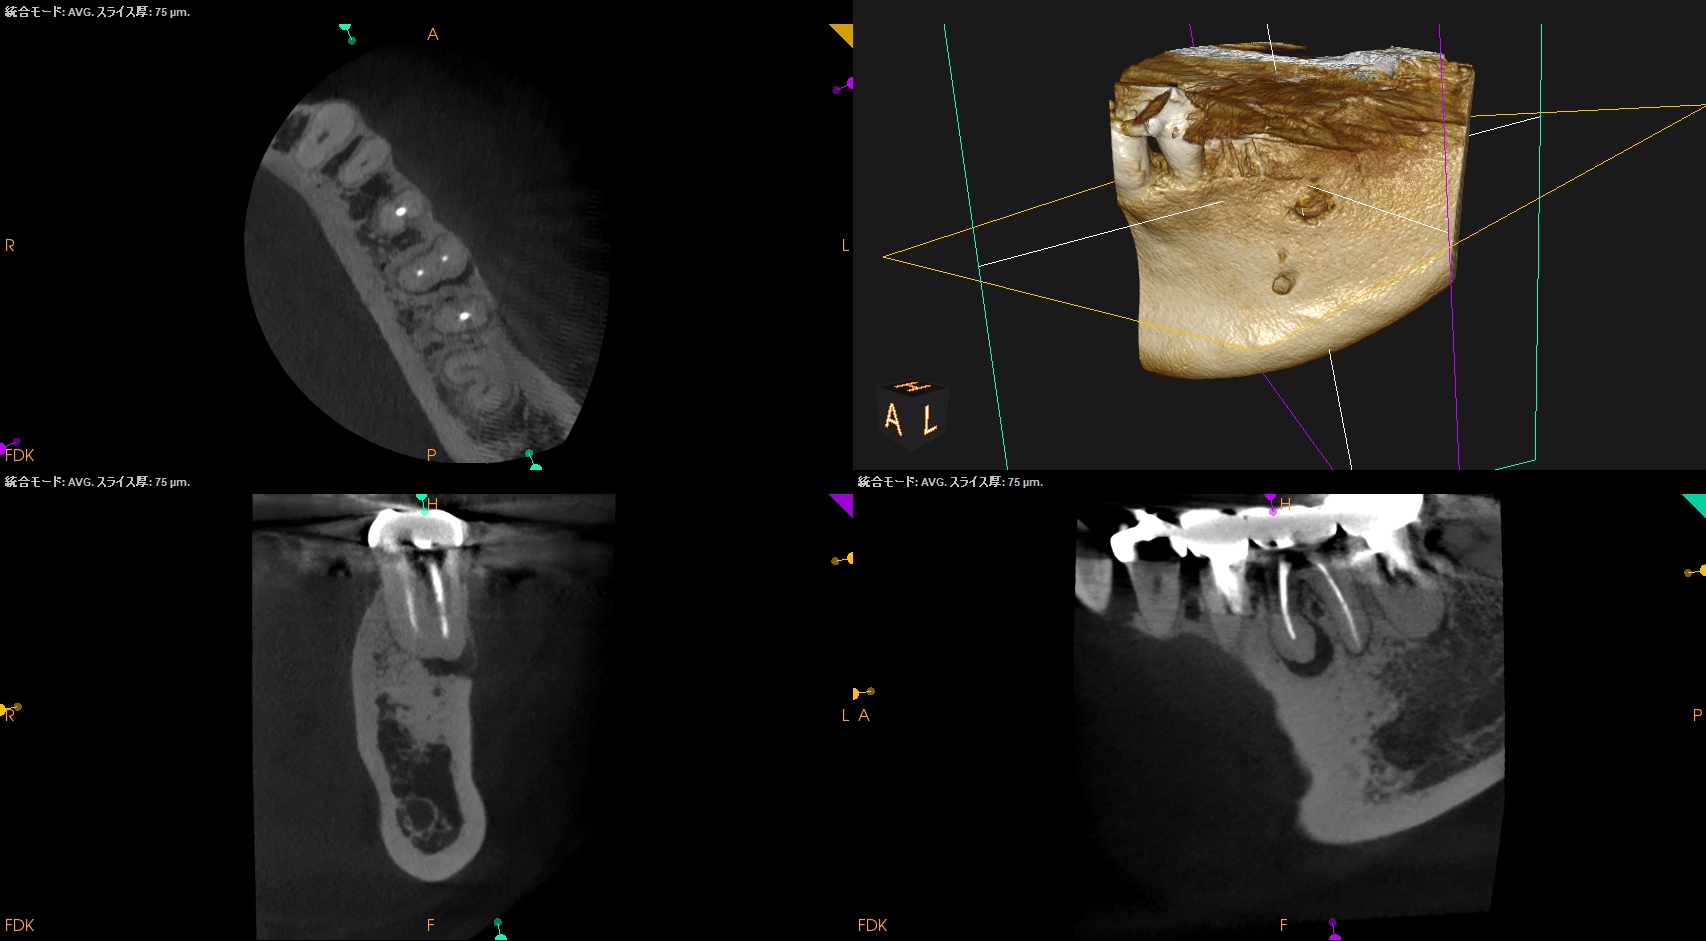

Pre-op CBCT(2025.1.10)

MB

ML

D

根尖病変があるのは近心根のみであるので近心根のみ再根管形成することにした。

その際は、

MBもMLも穿通させる必要があることがCBCTを見える絵にしていけばわかる。